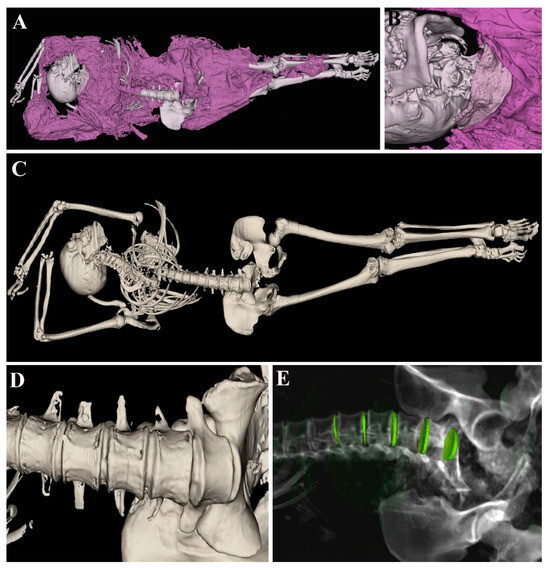

2. Materials and Methods

2.1. Samples

2.2. Anatomage Table

3. Results